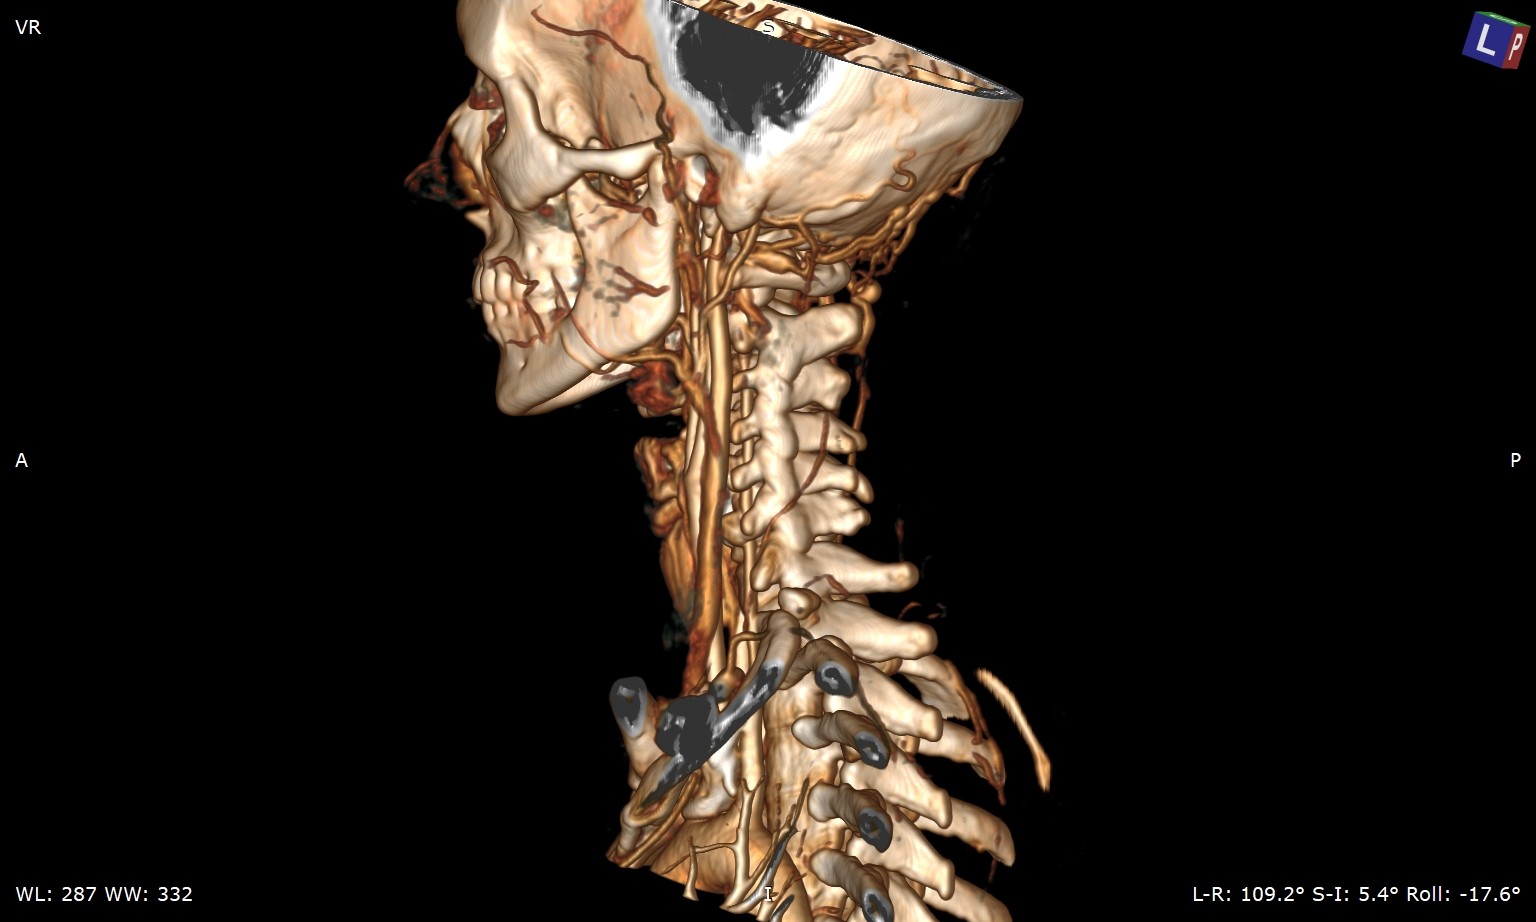

So my daughter had her icp monitoring done two days ago. They kept her at Hopkins until this evening and the results have not been officially given although they said that the fluctuations in her head pressure were not enough to consider it a problem with her csf so that is a good thing. Her pressure did rise significantly whenever she bent over or when her head went below her heart. Now we are left with the real possibility that the pressure has been coming from her jugular vein compression all along. We have a telecall with Dr. Costantino in early March so hopefully he will be able to look at her imaging and confirm that she does have compression at the C1 level. I’m not sure that her styloids are part of the equation but I think it is clear from the imaging that the C1 is involved. I’m going to upload many of her images that I was able to make into 3d with RadiAnt but I’m not sure how good they are. I would appreciate anyone who can view them to give me their opinion on anything they may see that could be causing her head pressure. I did include some 2D images as well because they do seem to show the C1 compression of the jugular.

I’ve annotated a couple of the images you posted & will explain what I see under each image.

On the left side, your daughter’s IJV looks compressed at the styloid/skullbase level, possibly at C1 then lower between C4-C6. Because her cervical spine is so straight, it almost appears the transverse processes of those 3 vertebrae are in contact with her IJV & even below them. She has quite a number of collateral veins in the area of her skull base which is an indication of IJV compression. Though I can’t see the very tip of the greater horn of her hyoid bone on this side, it almost looks like it could be in contact with her external carotid artery (ECA) which can cause different symptoms than the IJVs.

There are very similar situations with the right side though I can’t see enough of the hyoid bone on this side to comment about the right greater horn.

Her compression doesn’t look severe, but since she’s symptomatic, the compression is enough for her body to be reacting to it. That Hopkins confirmed its not high enough to be a problem is good & bad. Good because she’s at lower risk for a CSF leak, but bad because I feel, in some respect, they were saying IH isn’t causing her symptoms which it most likely is.

Thank you so much for looking at these scans and for pointing out the possible issues and labeling them so well. The details really help. I can say that her vascular surgeon, Dr. Khanjan Nagarsheth at the University of Maryland Medical Center has scheduled her for a jugular vein decompression surgery in mid March. He did a venogram of her jugulars and found that both sides are 97% compressed around the C5-C6 level. She had a fusion in this area in 2021 and he believes the veins are being compressed by scar tissue probably from that surgery. He said he thought there was going to be compression around the C1 area as well due to the cta images but he didn’t find this to be true during the venogram. I am not convinced that there is no compression there so we decided to continue to find other docs who focus on any neck compression issues that could be present. Isaiah_40_31 I also am concerned about the neuro docs at Hopkins saying her mmhg pressures were of no concern because of some of the high numbers that were recorded when she was bending over especially. They were well above what is normal for people who are exercising but they were only concerned about certain aspects of the recordings. They did acknowledge that they believe her when she describes her head pressure etc but they were only checking for potential csf leaks if I’m understanding them correctly. We’re glad that is off the table but it bothers me that they don’t know what is causing it and so far have not figured out what the next step should be to figure it out. I am convinced it is compression in her neck and skull base. Some of the drs have said they think that that could be the case but dont want to say anything definite. Dr. Nagarsheth is doing one side and then the other 6 months apart and may possibly need to put a stent in her vein. We would like to avoid that since he said he would be putting her on a strong blood thinner and she would not be able to come off of it for a year. So we are hoping that Dr. Costantino will see compression issues that he wants to address and we may have to postpone her surgery with Dr. Nagarsheth if Costantino can do all of what may need to be done. Add her wedding to the end of April and there’s alot going on right now. Dr. Nagarsheth said she has alot of large collateral veins which tells him this has been going on for quite awhile. Isaiah_40_31 I find it interesting that you are spot on with the collaterals as well as the compression between the C4-C6 area. That must be what he found in the venogram. Do her styloids appear to be wider than what I normally see on diagrams? They don’t appear to be very long but maybe the width is a problem in her case

Her styloids are very wide at the skull base & are not very well defined. I think that’s why her IJVs looked compressed to me right at the styloid/skull base junction, but you’ll need to see what Dr. Costantino thinks.

I agree that her styloids do look pretty chunky at the skull base, so it’s worth seeing what Dr C says, but be prepared for the compression further down to still be an issue? Stenting should be a last resort I felt personally, I’ve been very lucky that my IJVs opened up enough after surgery to resolve the head pressure…